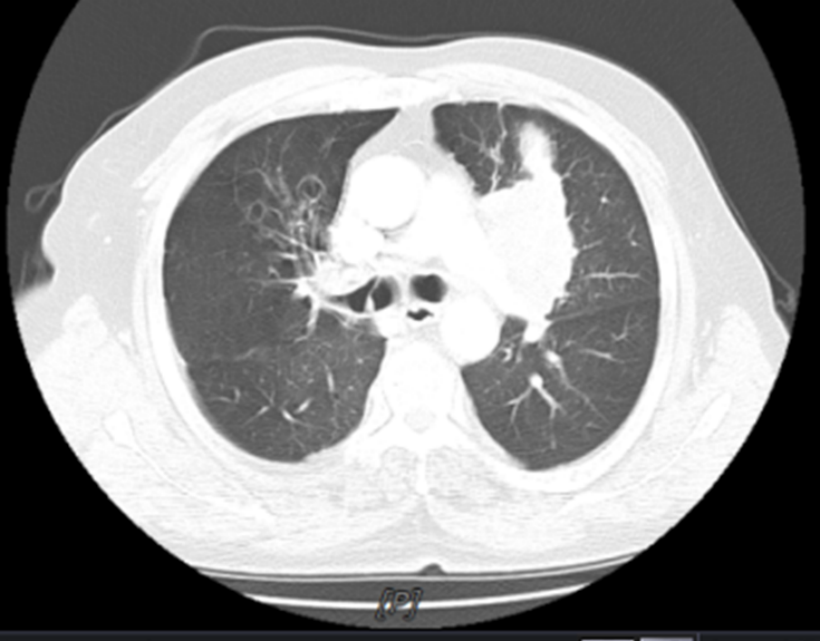

2024年3月8日,患者复查发现锁骨上淋巴结转移进展(图4)。KPS评分:70分,患者拒绝静脉化疗,因经济原因未使用免疫治疗。

14.9.png

图4 颈部淋巴结超声(2024-03-08)

疗效评估:PD。

PFS1:12个月。